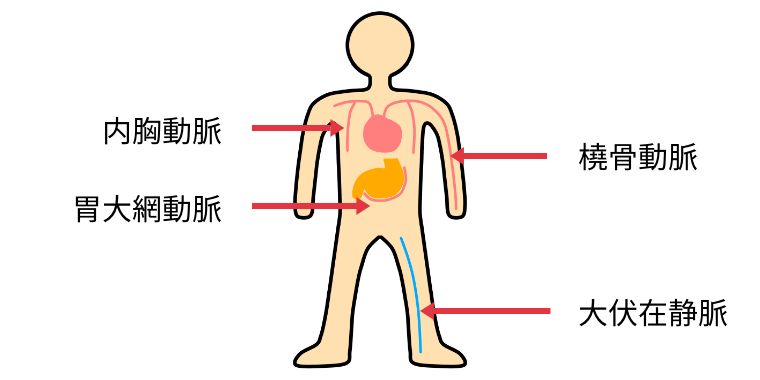

狭心症や心筋梗塞で、狭くなったり詰まった血管の先に新しい血管(グラフト)をつなぎ、血流の迂回路(バイパス)をつくる手術が冠動脈バイパス手術(CABG)です。

バイパスには基本的に以下の血管(グラフト)を使用します。最も重要な冠動脈である左前下行枝には、主に長期開存性に優れた内胸動脈をグラフトに使用します。その他の冠動脈についてはグラフトを組み合わせてバイパスのデザインを行います。

当院では、長期成績が良好と言われる両側の内胸動脈を積極的に使用しています。